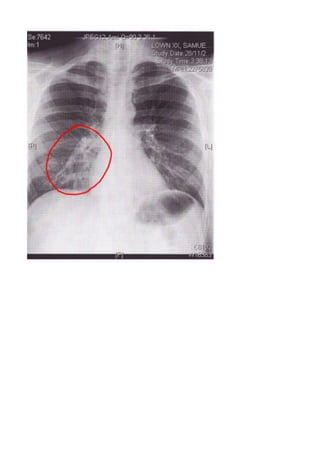

A chest X-ray is often taken if bronchitis is suspected to help rule out other lung conditions such as pneumonia,

tuberculosis, or bronchial obstructions.